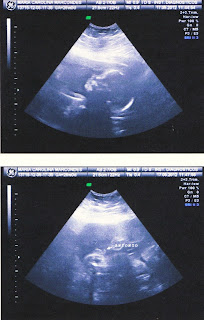

Também fomos ao cardiologista que foi um porre pra conseguir, (logo mais abaixo conto e aproveito pra reclamar), bem, levei ele ao cardio, ele o examinou, falou que acha que não é nada, mas vamos fazer um ecocardiograma pra verificar. Pra quem não leu os posts anteriores meu filhote tem um sopro no coração, que é muito comum e costuma sumir até o 6º mês, estamos na torcida pra que seja o caso do Antônio. Mas como disse anteriormente estou confiante que não é nada, meu baixinho é guerreiro, passamos tanta coisa na gravidez e superamos sem marcas não é mesmo?! Então não é agora que vamos cambalear.